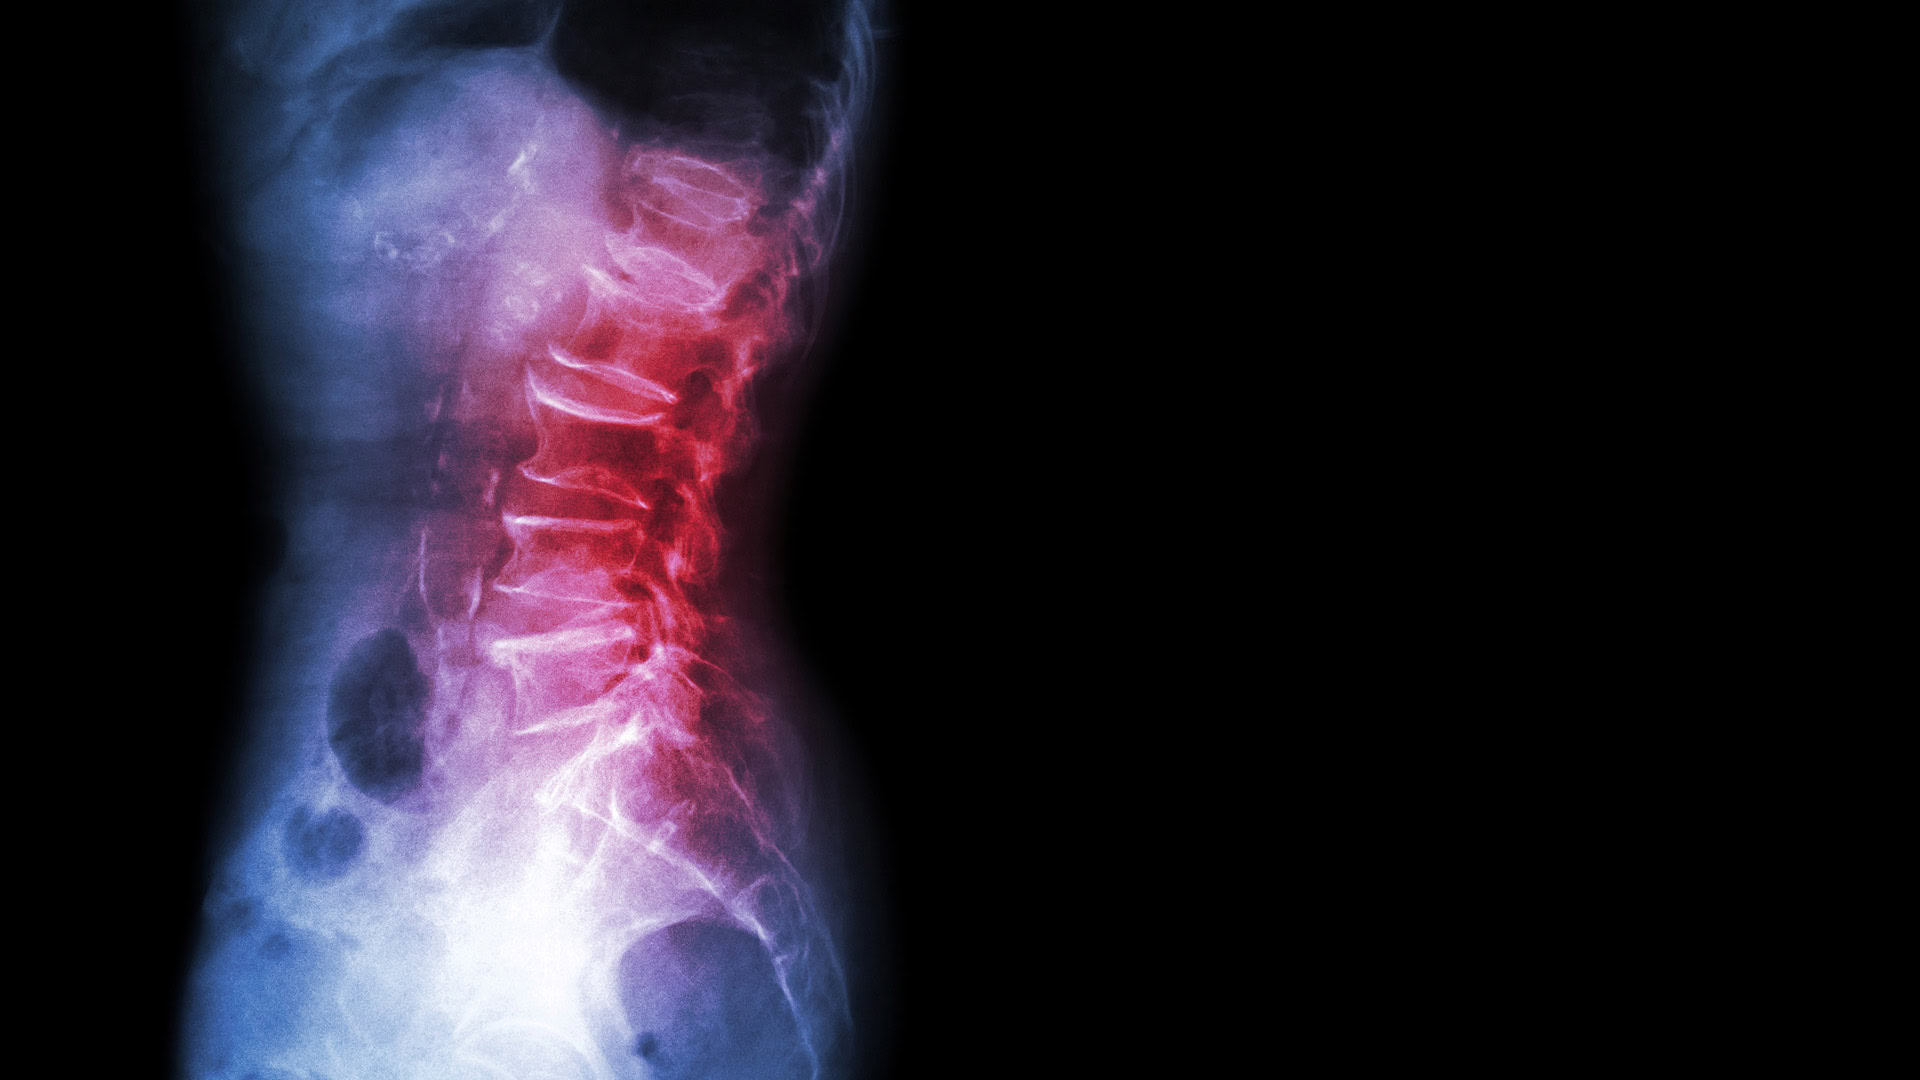

X-ray showing spondylolisthesis in lumbar spine